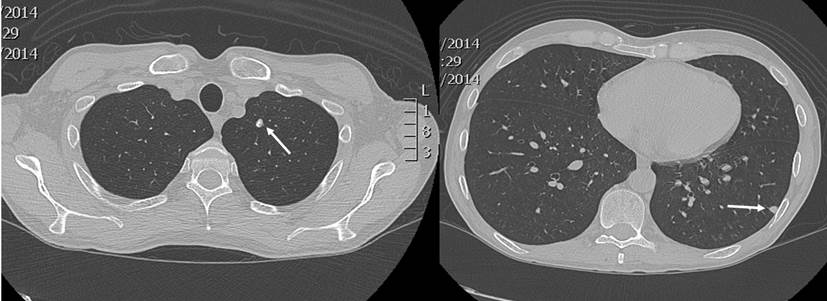

En un nuevo control endoscópico, se encontró pancolitis ulcerativa y pseudopólipos, que en comparación con la colonoscopia previa, evidenció una progresión de la enfermedad, por lo que se contempló el inicio de una terapia biológica. Se solicitaron pruebas de tuberculina (Purified protein derivative, PPD), serología para hepatitis A, B, C y una prueba de VIH. Se realizó además una radiografía de tórax, en la que se observó la presencia de un nódulo en el lóbulo superior izquierdo y otro en el lóbulo inferior, de 6 mm cada uno (Figura 1). La tomografía computadorizada de tórax confirmó dichos hallazgos (Figura 2).

Ante la sospecha de un tuberculoma, se realizó una biopsia en cuña del nódulo del lóbulo inferior, con una patología que reportó un parénquima pulmonar con enfermedad granulomatosa crónica caseificante, compatible con criptococosis, y negativo para bacilos acidorresistentes (BAAR) (Figura 3). Los cultivos de hongos confirmaron un moderado crecimiento de Cryptococcus neoformans, mientras que la PPD negativa descartó la tuberculosis latente.

Nuestro paciente no presentó síntomas relacionados con la criptococosis. Por tanto, el diagnóstico fue incidental, a partir del hallazgo inicial de nódulos pulmonares que se confirmaron mediante tomografía. Esta técnica forma parte de los métodos diagnósticos y en ella, usualmente, se observan pocos o múltiples nódulos subpleurales o masas con o sin halo. Además, en un menor número de casos, pueden apreciarse consolidaciones, derrames pleurales o un aumento del tamaño de los ganglios mediastínicos 10,11.